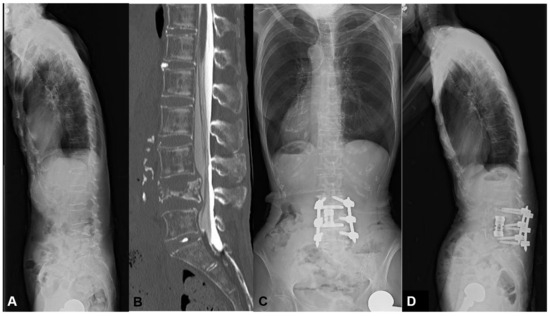

3.1.3. Case 3: 78 Years Old, Female, L4 Vertebral Collapse

The patient suffered from L4 compression fracture 4 months ago. The gait disturbance progressed with the weakness of lower extremities due to neural compression of vertebral collapse. The MIS L4 corpectomy followed by percutaneous screw fixation was conducted, resulting in the recovery of motor loss and gait disturbance. (Figure 6) In this case, we conducted short-segment fusion because of no LK and low PI of 42 degrees. After surgery, the LK was zero degrees with a postoperative mismatch of 30 degrees. These values were within our obtained threshold of 40 degrees, leading to no MC.

Figure 6.

A 78-year-old female suffering from L4 vertebral collapse. The MIS L4 corpectomy followed by percutaneous screw fixation was conducted, resulting in the recovery of motor loss and gait disturbance without mechanical complications. (A) Preoperative lateral X-ray, (B) Preoperative myelogram CT, (C) Standing AP X-ray at one year postoperatively, (D) Standing lateral X-ray at one year postoperatively.